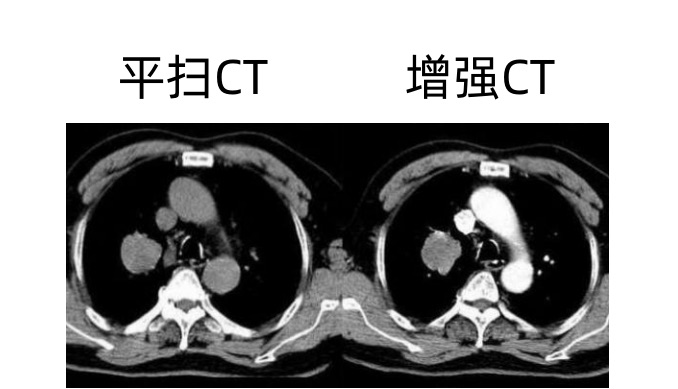

我们先来看CT,CT检查是根据人体不同部位器官的密度不同,对射线吸收的程度不同,再通过电脑对这一信息处理后形成的一组图像。医生就可以根据这些影像对患者的身体情况做出诊断。但人体在有些部位或器官上的密度本身差别不大,CT不能够把它们区分出来,形成具有诊断价值的图像。这一情况就是“药水”派上用场的时候了。CT增强检查时所使用的药物其实是一种X线对比剂。它的本质是一种水溶性含碘制剂,利用碘对X线的高吸收特性,可以提高对比剂所在组织的对比度,帮助区分出一块区域内不借助X线对比剂,本来不明显的结构,帮助医生诊断。